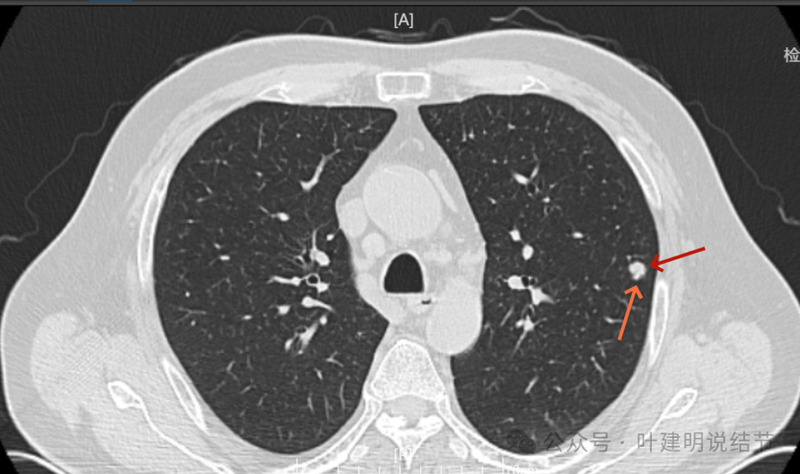

少许偏磨玻璃成分,灶边细支气管扩张。

细支气管扩张与实性密度。

边缘区也有细支气管扩张,说明病灶有收缩力,影响邻近细支气管。

明显实性成分,灶边的细支气管有扩张。

边上有细支气管扩张。